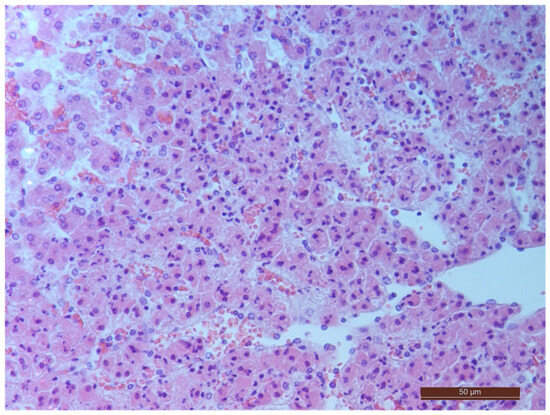

3.2. Pathology of the Liver

3.4. Pathology of Kidneys